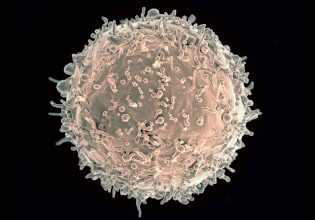

Σε χαμηλές θερμοκρασίες όπως μια θερμοκρασία περιβάλλοντος 27 βαθμών Κελσίου δεν βλέπουμε τα πράγματα να εκπέμπουν κάποια λάμψη. Ούτε εμείς με σωματική θερμοκρασία 37 βαθμών λάμπουμε σαν πυρακτωμένο κομμάτι σίδερο. Η όλη καμπύλη μας και το μήκος κύματος της μέγιστης έντασης βρίσκονται σχεδόν αποκλειστικά στην αόρατη για το μάτι περιοχή. Και δεν μπορούμε να πούμε κοιτάζοντας έτσι απλά τον άλλον αν η θερμοκρασία του είναι 36,6 ή 39 βαθμοί Κελσίου. Η ακτινοβολία που εκπέμπει είναι στην περιοχή του αόρατου υπερύθρου, με μήκος κύματος κάπου κοντά στα 9,5 εκατομμυριοστά του μέτρου.

Γενικά όμως τα περισσότερα αντικείμενα γύρω μας και εμείς οι ίδιοι δεν συμπεριφερόμαστε ως τέλεια μέλανα σώματα. Το φως που εκπέμπουμε είναι μείγμα από ανακλώμενο, που έρχεται δηλαδή, χτυπάει επάνω μας και φεύγει, και από αυτό που παράγεται από τα μόρια του δικού μας σώματος και έχει άμεση σχέση με τη θερμοκρασία μας.

Για κάθε σώμα λοιπόν, αν θέλουμε να βρίσκουμε τη θερμοκρασία του όχι μέσω της επαφής με ένα συνηθισμένο θερμόμετρο, χρειάζεται να καταφύγουμε στο «μείγμα» ακτινοβολιών που αναφέραμε πριν, διότι αυτό έχει άμεση σύνδεση με τη θερμοκρασία. Υπάρχει μάλιστα και βοηθάει στους υπολογισμούς ένας συντελεστής εκπομπής που παίρνει τιμές από περίπου 0 για εντελώς ανακλαστικές επιφάνειες, έως 1 για κάτι που συμπεριφέρεται ως μέλαν σώμα. Για παράδειγμα, μια γυαλιστερή χρωμιωμένη επιφάνεια έχει συντελεστή 0,1, το τσιμέντο 0,54, το ανθρώπινο δέρμα 0,95-0,98 (βλέπε και εδώ: https://www.thermoworks.com/emissivity-table).